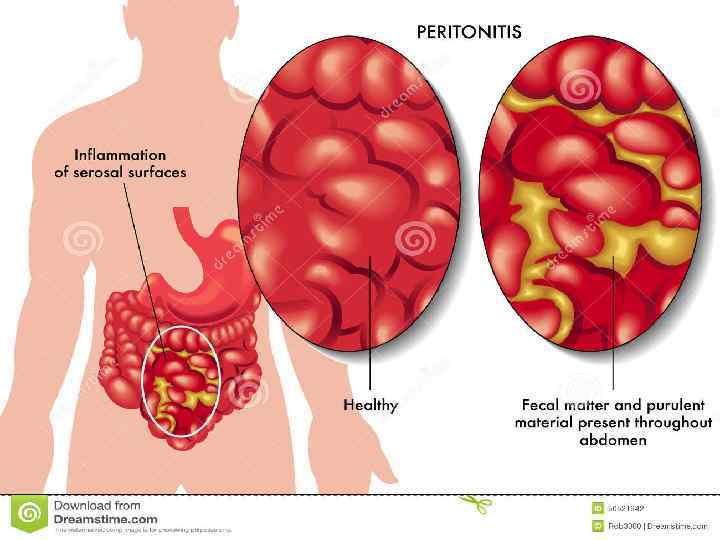

Іш қуысының және іш артының жарақаттарында жүргізілетін рентгенологиялық зерттеу әдісінің мақсаты, ол іштегі бос газдың (пневмоперитонеум, пневморетроперитонеум) немесе сұйықтықтың (гемоперитонеум) жүруіне, яғни олардың паренхиматозды ағзалардың(бауыр, көкбауыр, бүйрек) формасының өзгеруіне, және контурының анық болмауына алып келеді. Іш қуысының жарақатына азқазан-ішек тракттарының функциональды өзгерістері, деформациясы, дифрагманың жылжымалығы шектелуі де жатады. Асқазан-ішек тракттарының жарақатымен стационарға уақытында келмеген науқаста перитонит пен іш артының флегмонасының белгілері анықталуы мүмкін.